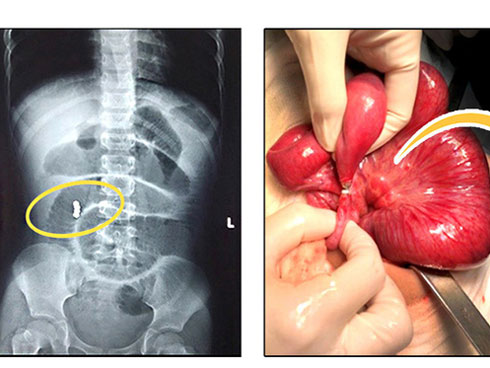

Sau gần 3 giờ, các phẫu thuật viên đã loại bỏ hoàn toàn dị vật, khâu kín vị trí ruột thủng thành công. Sau mổ, trẻ cần nhịn ăn, nuôi dưỡng bằng đường tĩnh mạch, sức khoẻ tạm thời ổn định, tuy nhiên vẫn cần theo dõi thêm.

25 viên bi nam châm trong ổ bụng